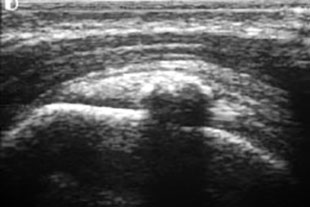

Kalkdepot im Ultraschallbild

Im Röntgenbild und in der Sonographie des Schultergelenkes finden sich Kalkeinlagerungen, zumeist in der Supraspinatussehne (Teil der Rotatorenmanschette) von unterschiedlicher Beschaffenheit und in verschiedenem Ausbreitungsgrad.